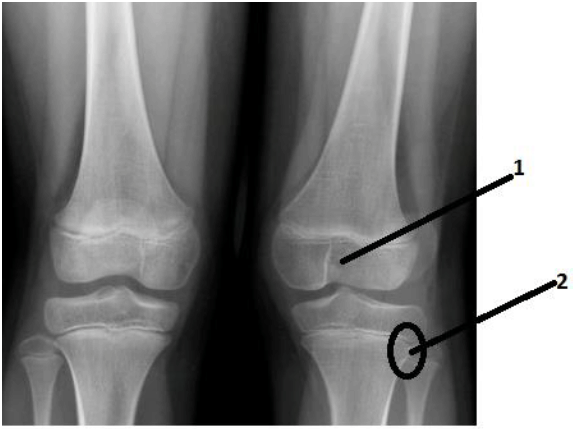

A imagem radiológica, abaixo, mostra:

A imagem radiológica, abaixo, mostra: